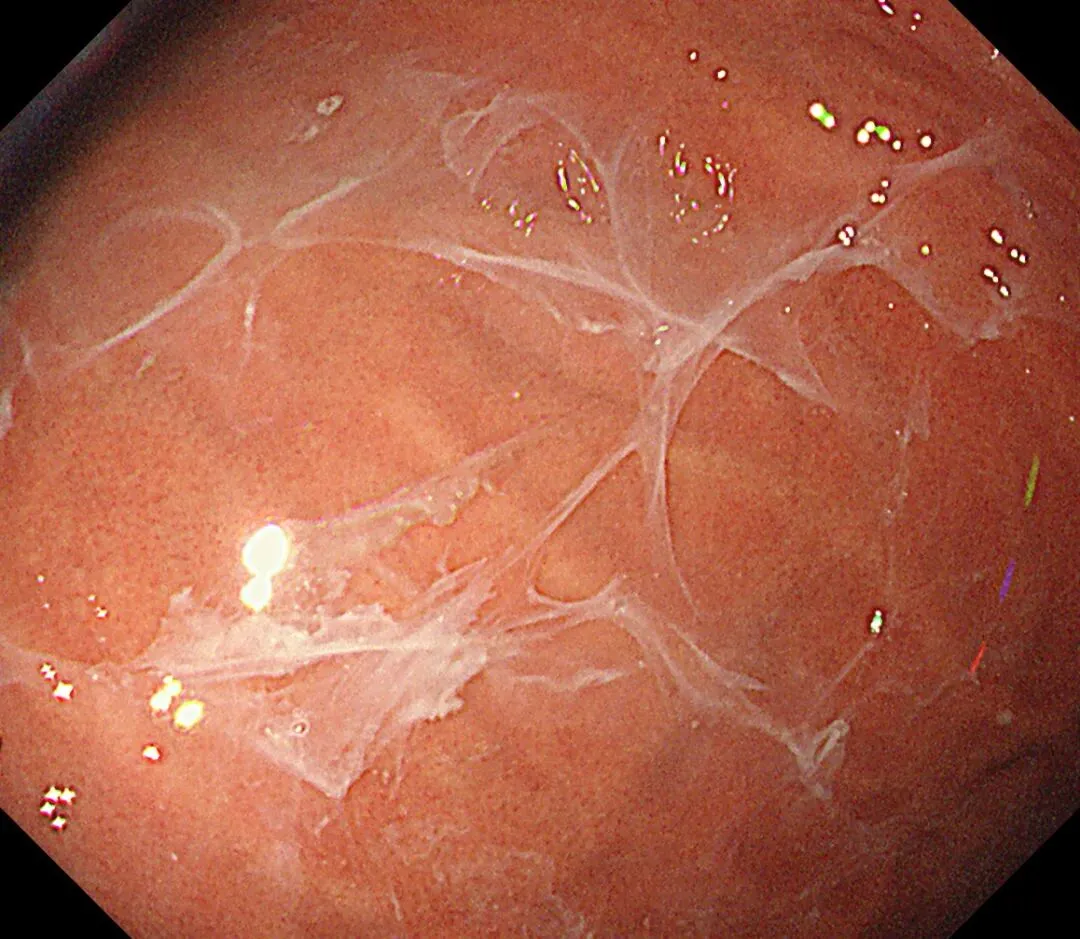

蛛网状黏液(web-like mucus):以胃底、胃体大弯为中心,有时可见白色透明、水洗难以去除的黏液附着,因外观与蜘蛛网相似而命名,多见于口服钾离子竞争性酸阻滞剂(P-CAB)患者,可能是因为其强效、持续抑酸作用所致,具体机制尚需进一步研究明确。

蛛网状黏液case3,服用P-CAB药物(具体服用时长不详)👇

个人体会:蛛网状黏液与P-CAB药物相关,顽固性黏液与AIG相关,两种胃内环境都一样是胃酸缺乏,据说胃内PH升高可导致蛋白质变性形成“乳状”黏附,也据说是因为胃酸缺乏导致化生的黏液分泌细胞大量增多,分泌异常成分的高粘稠度黏液,两者的形成机制和内镜表现是比较类似的,不同之处在于蛛网状黏液除了比较“网状”之外,还比较“拉丝”、“乳白”,顽固性黏液比较“果冻”、“淡白”、"广泛涂层"、“紧贴大地”。。。词穷了,从小没学过语文课,还需多看书、观察更多病例加以总结,请各位老师们指正。。。